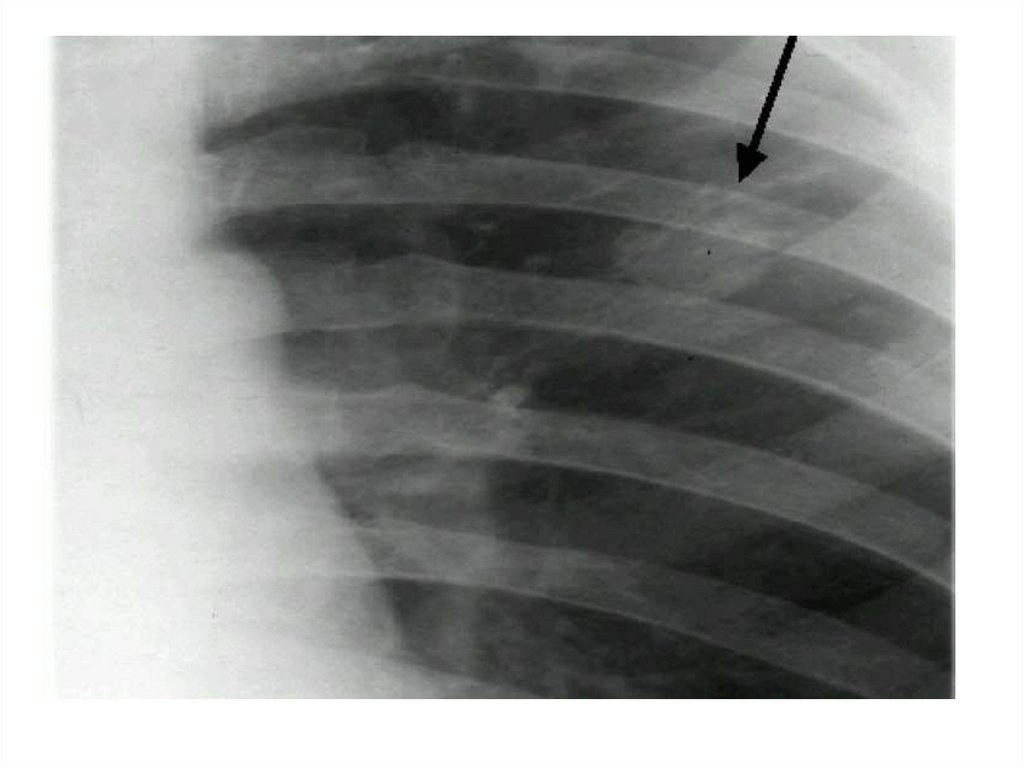

Рентгенограмма № 4

33. Рентгенограмма № 4